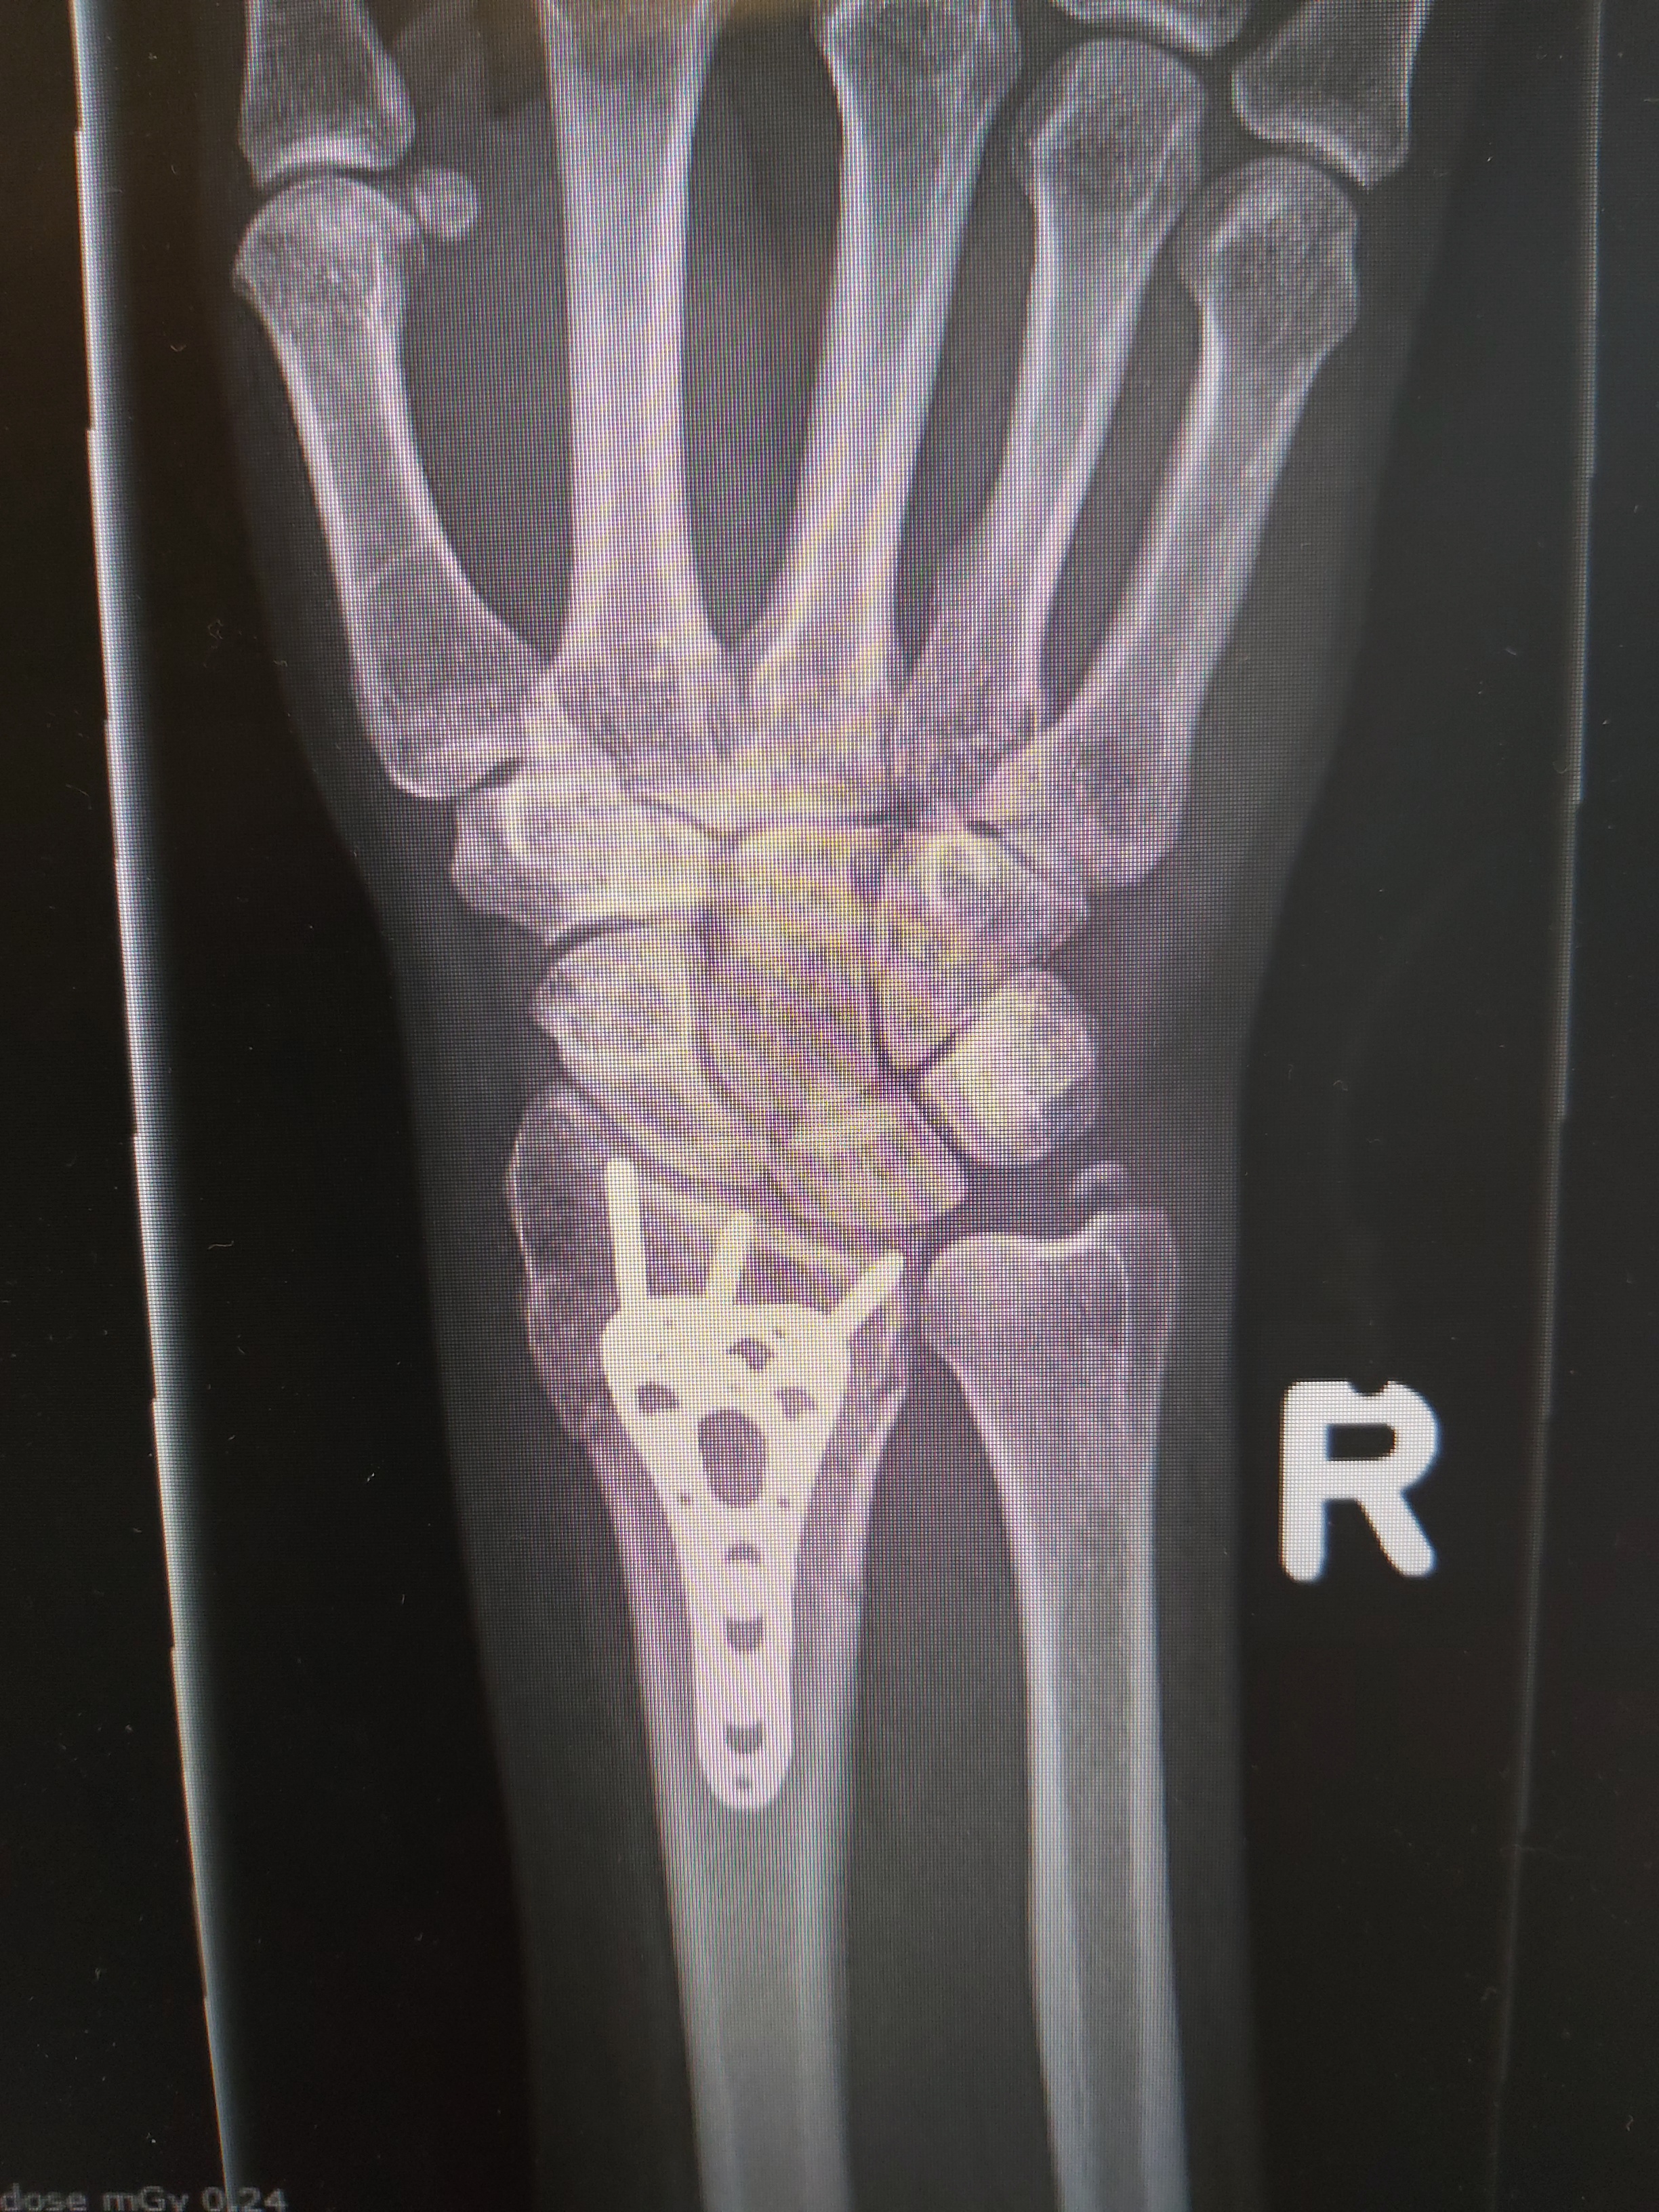

Genezing

Normaal geneest een factuur, afhankelijk van de gekozen behandeling, in 6 tot 12 weken. U heeft dan recht om een half jaar fysiotherapie, middels een verwijzing. Wanneer het echter nodig is dat een breuk operatief wordt behandeld. Dan ziet het herstel er al weer heel anders uit. Dan heeft u recht op een chronische verwijzing fysiotherapie voor een jaar. Niet dat u die altijd nodig heeft, maar is sommige gevallen helaas wel.